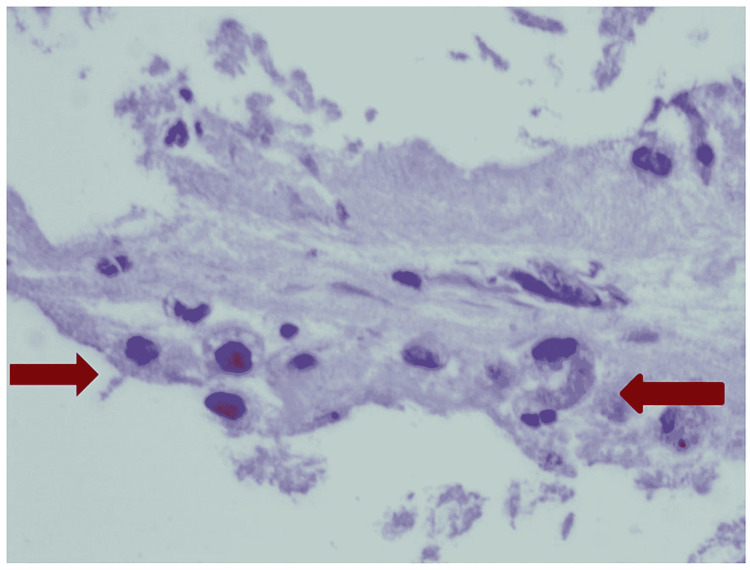

Cultures were negative, and an IV steroid was added. Bronchoscopy with BAL showed neutrophil-predominant lavage (WBC 331, neutrophil 57%, lymphocyte 13%, monocyte 30%) without any growth on cultures. BAL cytological assay showed intra-alveolar foamy macrophages (Figure 7). A transbronchial biopsy was remarkable for intra-alveolar macrophages with intracytoplasmic pigmentation and vacuolated cytoplasm (Figure 8). The course was complicated with a spontaneous pneumothorax requiring chest tube placement. After six days of mechanical ventilation, he was successfully extubated with the removal of the chest tube. Respiratory status continued to improve, and the patient was discharged on oxygen at 2 L/minute. The patient was discharged on a slow prednisone taper over a period of two months with pulmonary clinic follow-up. He was counseled about the importance of smoking and vaping cessation.